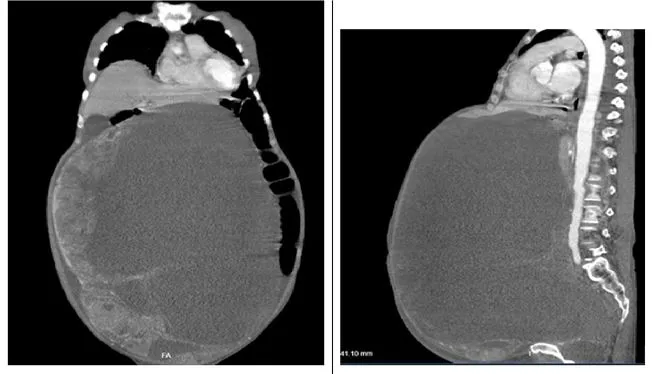

Bóc tách thành công khối u buồng trứng nặng 30kg cho cụ bà 78 tuổi ảnh 1 Hình ảnh khối u thể hiện trên CT-SCAN

Ca mổ khá khó khăn do u quá lớn (30x50cm, nặng 30kg) và dính nhiều vào ruột, thành bụng, tuy nhiên sau 2,5 giờ các bác sĩ cắt cắt trọn được khối u một cách an toàn.